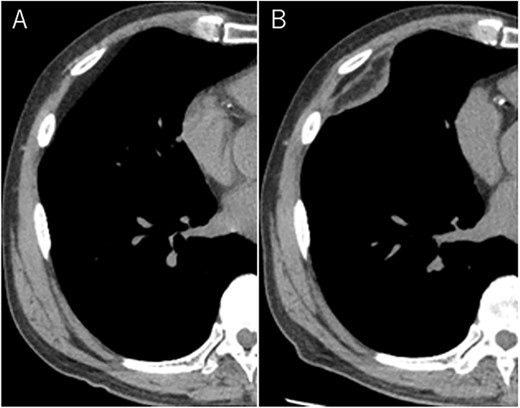

A 72-year-old man with a history of hypertension and left renal cancer (Stage I) was referred to us with a mass in the right chest wall on post-operative follow-up chest computed tomography (CT) for renal cancer. He had a smoking history of 20 pack-years and had no exposure to environmental fumes or dust. Physical examination results were unremarkable. The laboratory findings were within normal limits. Pulmonary function tests and cardiovascular examinations revealed normal results. Chest CT revealed mixed density mass (8.0 × 5.0 × 3.0 cm) located in front of thoracic wall in the third to sixth right intercostal space. The tumor can be revealed as thoracic wall fat (7.8 × 4.8 × 1.2 cm) on CT 1 year before (not considered as abnormal), and it was progressively increased in size and the density changed (Fig. 1A and B). Magnetic resonance imaging (MRI) showed a fatty mass of heterogenic density. T2 high foci (Fig. 2A) and irregular marginal enhancement of the tumor were observed (Fig. 2B). Maximal standard uptake value (SUVmax) of 18F-fluorodeoxyglucose positron emission tomography (FDG-PET) was 3.78 (Fig. 3). Based on these radiological image findings, we scheduled surgery with suspicion of liposarcoma. During the surgery, the patient was placed in the lateral decubitus position. We made 1.5-cm incision in the sixth intercostal space along the posterior axial line for thoracoscopy. We found dense adhesions between the chest wall tumor, lung (front part of all three lobes of the right lung) and diaphragm. We made a 30-cm incision in the fourth intercostal space and resected the tumor along with lung (wedge resection of the front part of all three lobes of the right lung), diaphragm and third to sixth ribs and intercostal muscle. The chest wall defect was 25 × 15 cm and the diaphragm defect was 8 × 5 cm. For reconstruction, the mesh was placed and sutured to the diaphragm and the chest wall. Pathological examination revealed the well-circumscribed tumor with fibrous adhesion between the ribs, lung and diaphragm (Fig. 4A). Microscopically, the tumor consisted of mature fat tissue. There were fat necrosis inflammatory changes in the marginal area of the tumor with foamy macrophages and multinucleated giant cells (Fig. 4B and C). Fluorescence in situ hybridization examination for murine double-minute 2 was negative. Based on these findings, a chest wall lipoma was diagnosed. The post-operative course was uneventful. The patient was followed up for 24 months without evidence of recurrence.

18F-FDG-PET uptake by the tumor; maximum standard uptake value was 3.78.

In the present case, tumor enlargement with heterogenic change of the density, thickened septa >2 mm, prominent foci of high T2 signal and prominent areas of enhancement on MRI were seen on preoperative CT and MRI. In addition, the SUVmax of FDG-PET was higher than that of simple lipoma (SUVmax = 3.78). These findings led to a misdiagnosis for liposarcoma. Furthermore, intraoperative findings of dense adhesion between the tumor and surrounding structures strengthen our suspicion of liposarcoma. We could not find another case of intrathoracic lipoma of the chest wall with density change on radiological image and dense adhesion between the surrounding structures.